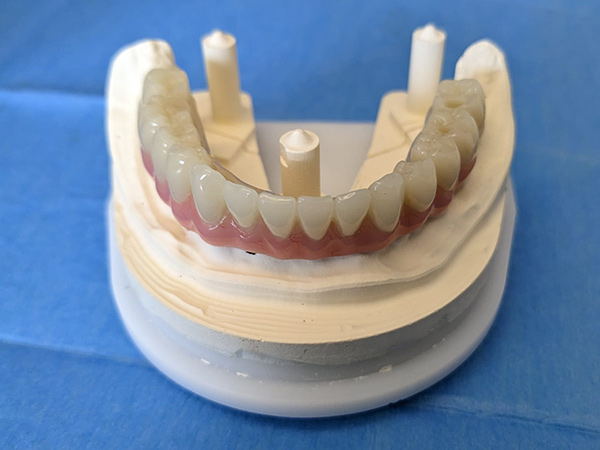

Il paziente era portatore di protesi totale inferiore diventata instabile nel tempo.

Sono state eseguite Tac con dima radiologica e progettazione per inserimento implantare tramite dima chirurgica di sei impianti AZ Implant tipo DX con overdenture a carico immediato.